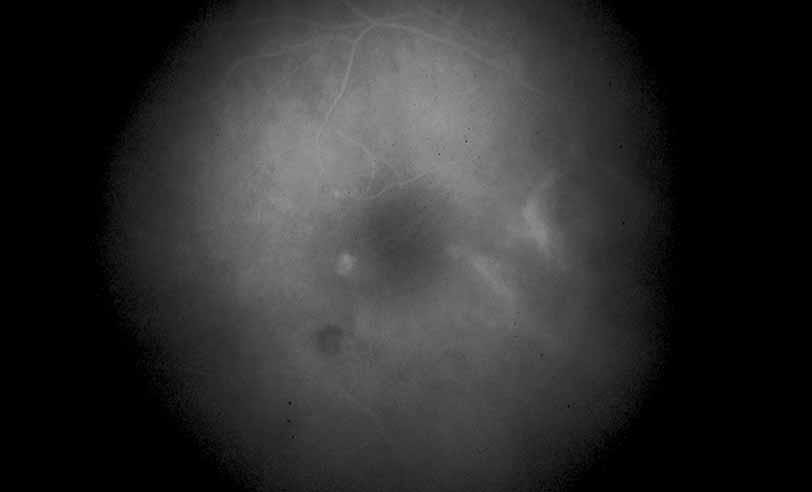

Fig. 6 Presumed ocular histoplasmosis. This patient developed decreased vision with mild vitritis. Color photograph shows a hazy view of the central macula.

Fig. 7 Presumed ocular histoplasmosis. Fluorescein angiogram of Figure 6 demonstrates cystoid macular edema as the cause of this patient's decreased vision.

Once a treatment regimen has been instituted, the follow-up fluorescein angiogram can serve as a marker for treatment response in addition to other clinical variables, including visual acuity and severity of intraocular inflammation (see Fig. 8).

Fig. 8 Presumed ocular histoplasmosis. Repeat fluorescein angiogram from Figure 7 shows complete resolution of cystoid macular edema after intravitreal injection of triamcinolone–acetamide.